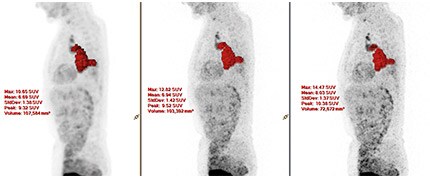

Images reconstructed with ×Fine for this lung cancer patient demonstrate enhanced lesion detectability.

Images courtesy of University Hospital Salzburg, Austria

×Fine and ×Sharp further contribute to image quality, seen here in enhanced resolution. ×Fine reconstruction (center) and ×Fine with ×Sharp reconstruction (far right).

In a whole-body patient test study conducted by researchers at the University Hospital Salzburg, Austria, ×Sharp helped enhance the visualization of small lesions. Applying ×Sharp led to an increase in the lesion SUVmax compared with scans performed without ×Sharp. The lesions in the patients were in the 12-20 mm range.

Image courtesy of University Hospital Salzburg, Austria